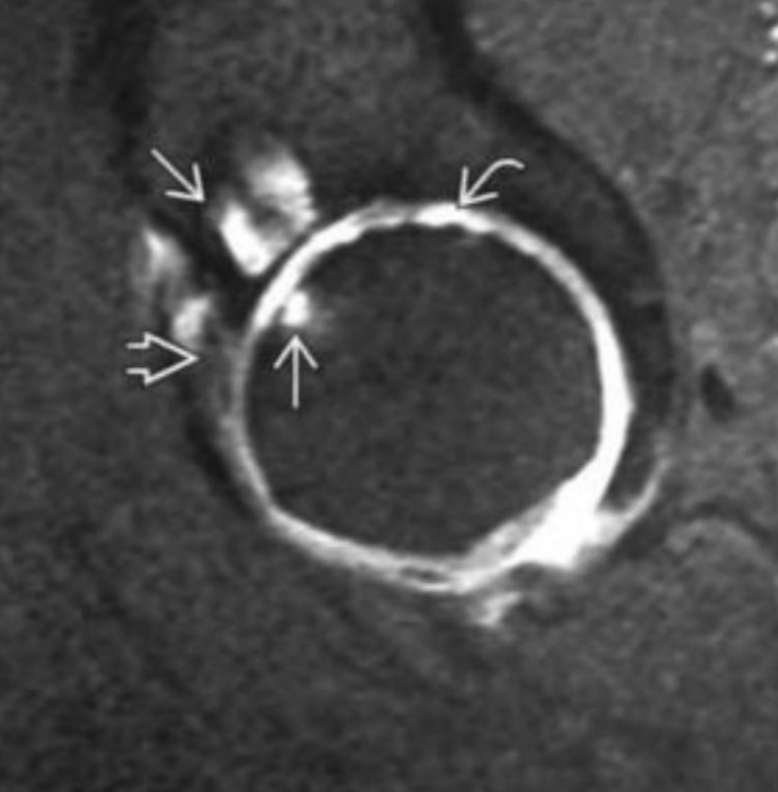

RM pinzamienro femoroacetabular

A

Edema óseo hiperintenso

Pinzamiento leve

Lesión del labrum

Edema hiperintenso